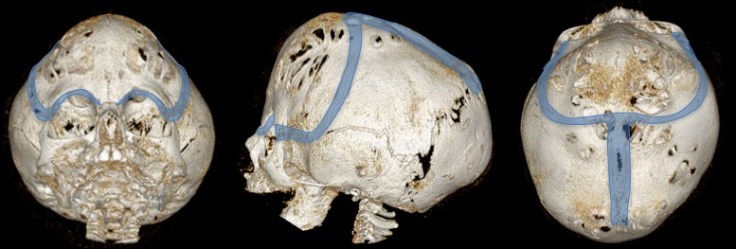

synonymes : cloverleaf skull ; kleeblattschädel

la craniectomie périfrontale

- incision de Cairns-unterberger, exposition en sous-galéal jusqu’aux rebords orbitaires

- craniectomie de part et d’autre de la suture sagittale jusqu’au lambda

- résection du cimier médian

la craniectomie péri-occipitale

elle est indiquée en première ou en seconde intention en fonction de la présentation clinique et radiologique. elle permet de lever la compression du carrefour veineux dural qui est à l’origine de l’hydrocéphalie et de l’hypertension intra-crânienne.

craniectomie à la gouge sous contrôle visuel pour ne pas léser la dure-mère- dégagement des sinus transverses et du torcular